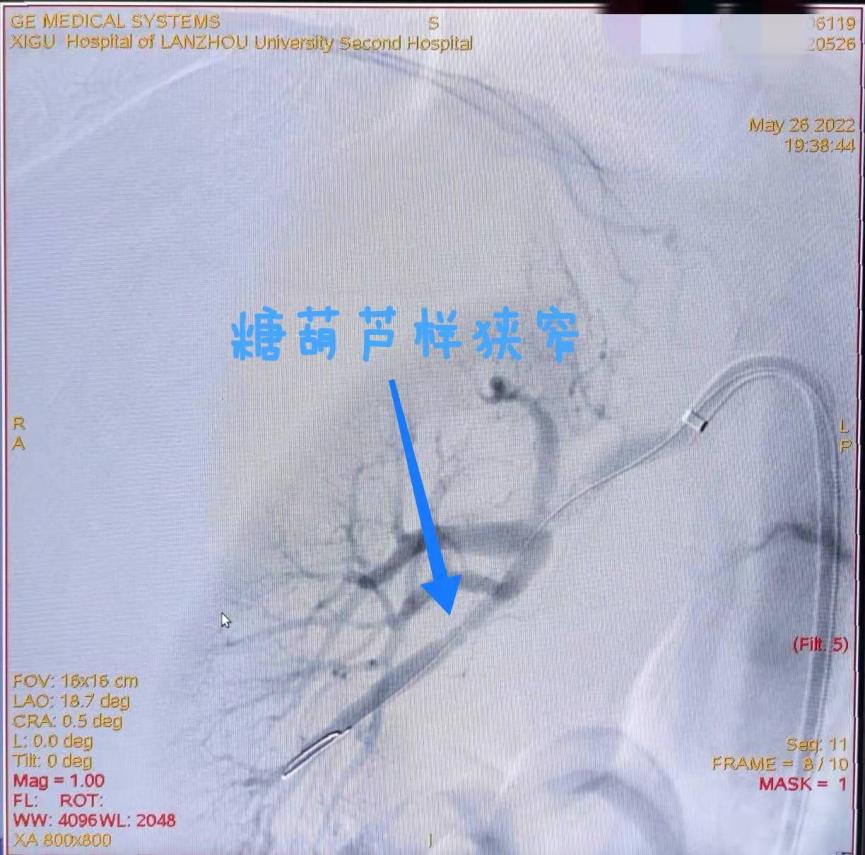

患者男性,38岁,发现血压升高40余天,血压最高达220/120mmHg,口服硝苯地平控释片60mg+缬沙坦氢氯噻嗪片联合降压,血压控制在140/80mmHg左右。入院后筛查高血压病因,肾动脉核磁共振检查提示右侧肾动脉狭窄,右肾轻度萎缩(图1),行肾动脉造影检查证实右侧肾动脉主干分叉处重度狭窄(图2、3)

结合患者临床表现及实验室检查、DSA检查,明确患者高血压病因为肾动脉狭窄所致,且患者已经出现右侧肾脏萎缩及肾功能不全,肾动脉狭窄原因考虑肌纤维肌性发育不良。经过我院神经外科黄普鑫团队讨论,在与患者及家属沟通后,决定为其实施经皮肾动脉球囊扩张成形术,解除肾动脉狭窄,以降低患者血压水平,预防高血压相关并发症,改善肾功能。手术顺利完成,术后患者肾动脉狭窄治疗效果显著(图4),血压恢复正常。